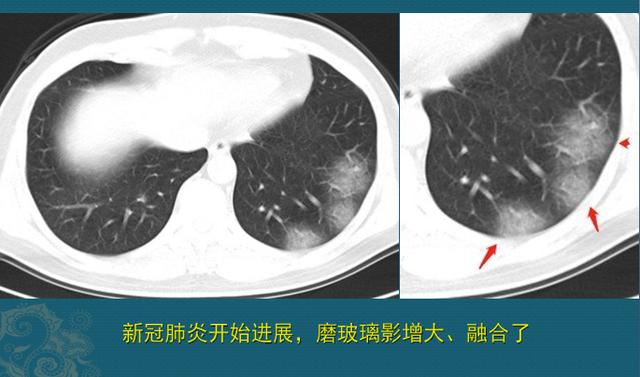

这种表现首先不符合肺癌。那么,大家最近都很关注新型冠状病毒肺炎,细心的读者会了解到,早期新冠肺炎就是肺内出现磨玻璃影,这位男士会不会是被新冠病毒感染了呢?

不是!有几个重要的CT鉴别点:

1.新冠病毒的磨玻璃影多为外周分布,内中带气腔分布的少见;

2.新冠肺炎少见胸腔积液、少见淋巴结肿大。如下图: